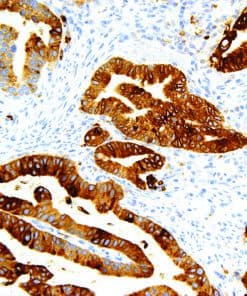

Thymidylate Synthase

Thymidylate Synthase (TS) is a crucial enzyme responsible for the synthesis of 2′-deoxythymidine-5′-monophosphate (dTMP) a precursor for thymidylate which is necessary for DNA replication and repair from 2′-deoxyuridine-5′-monophosphate (dUMP). In terms of cancer, TS is an important target for cancer treatment as the inhibition of TS and therefore nucleotide synthesis necessary for cell growth has shown to be a vital part for successful treatment against colorectal, pancreatic and breast cancers.

| Clone | IHC697 |

| Source | Mouse Monoclonal |

| Positive Control | Colon Cancer |

| Dilution Range | 1:100 – 1:400 |